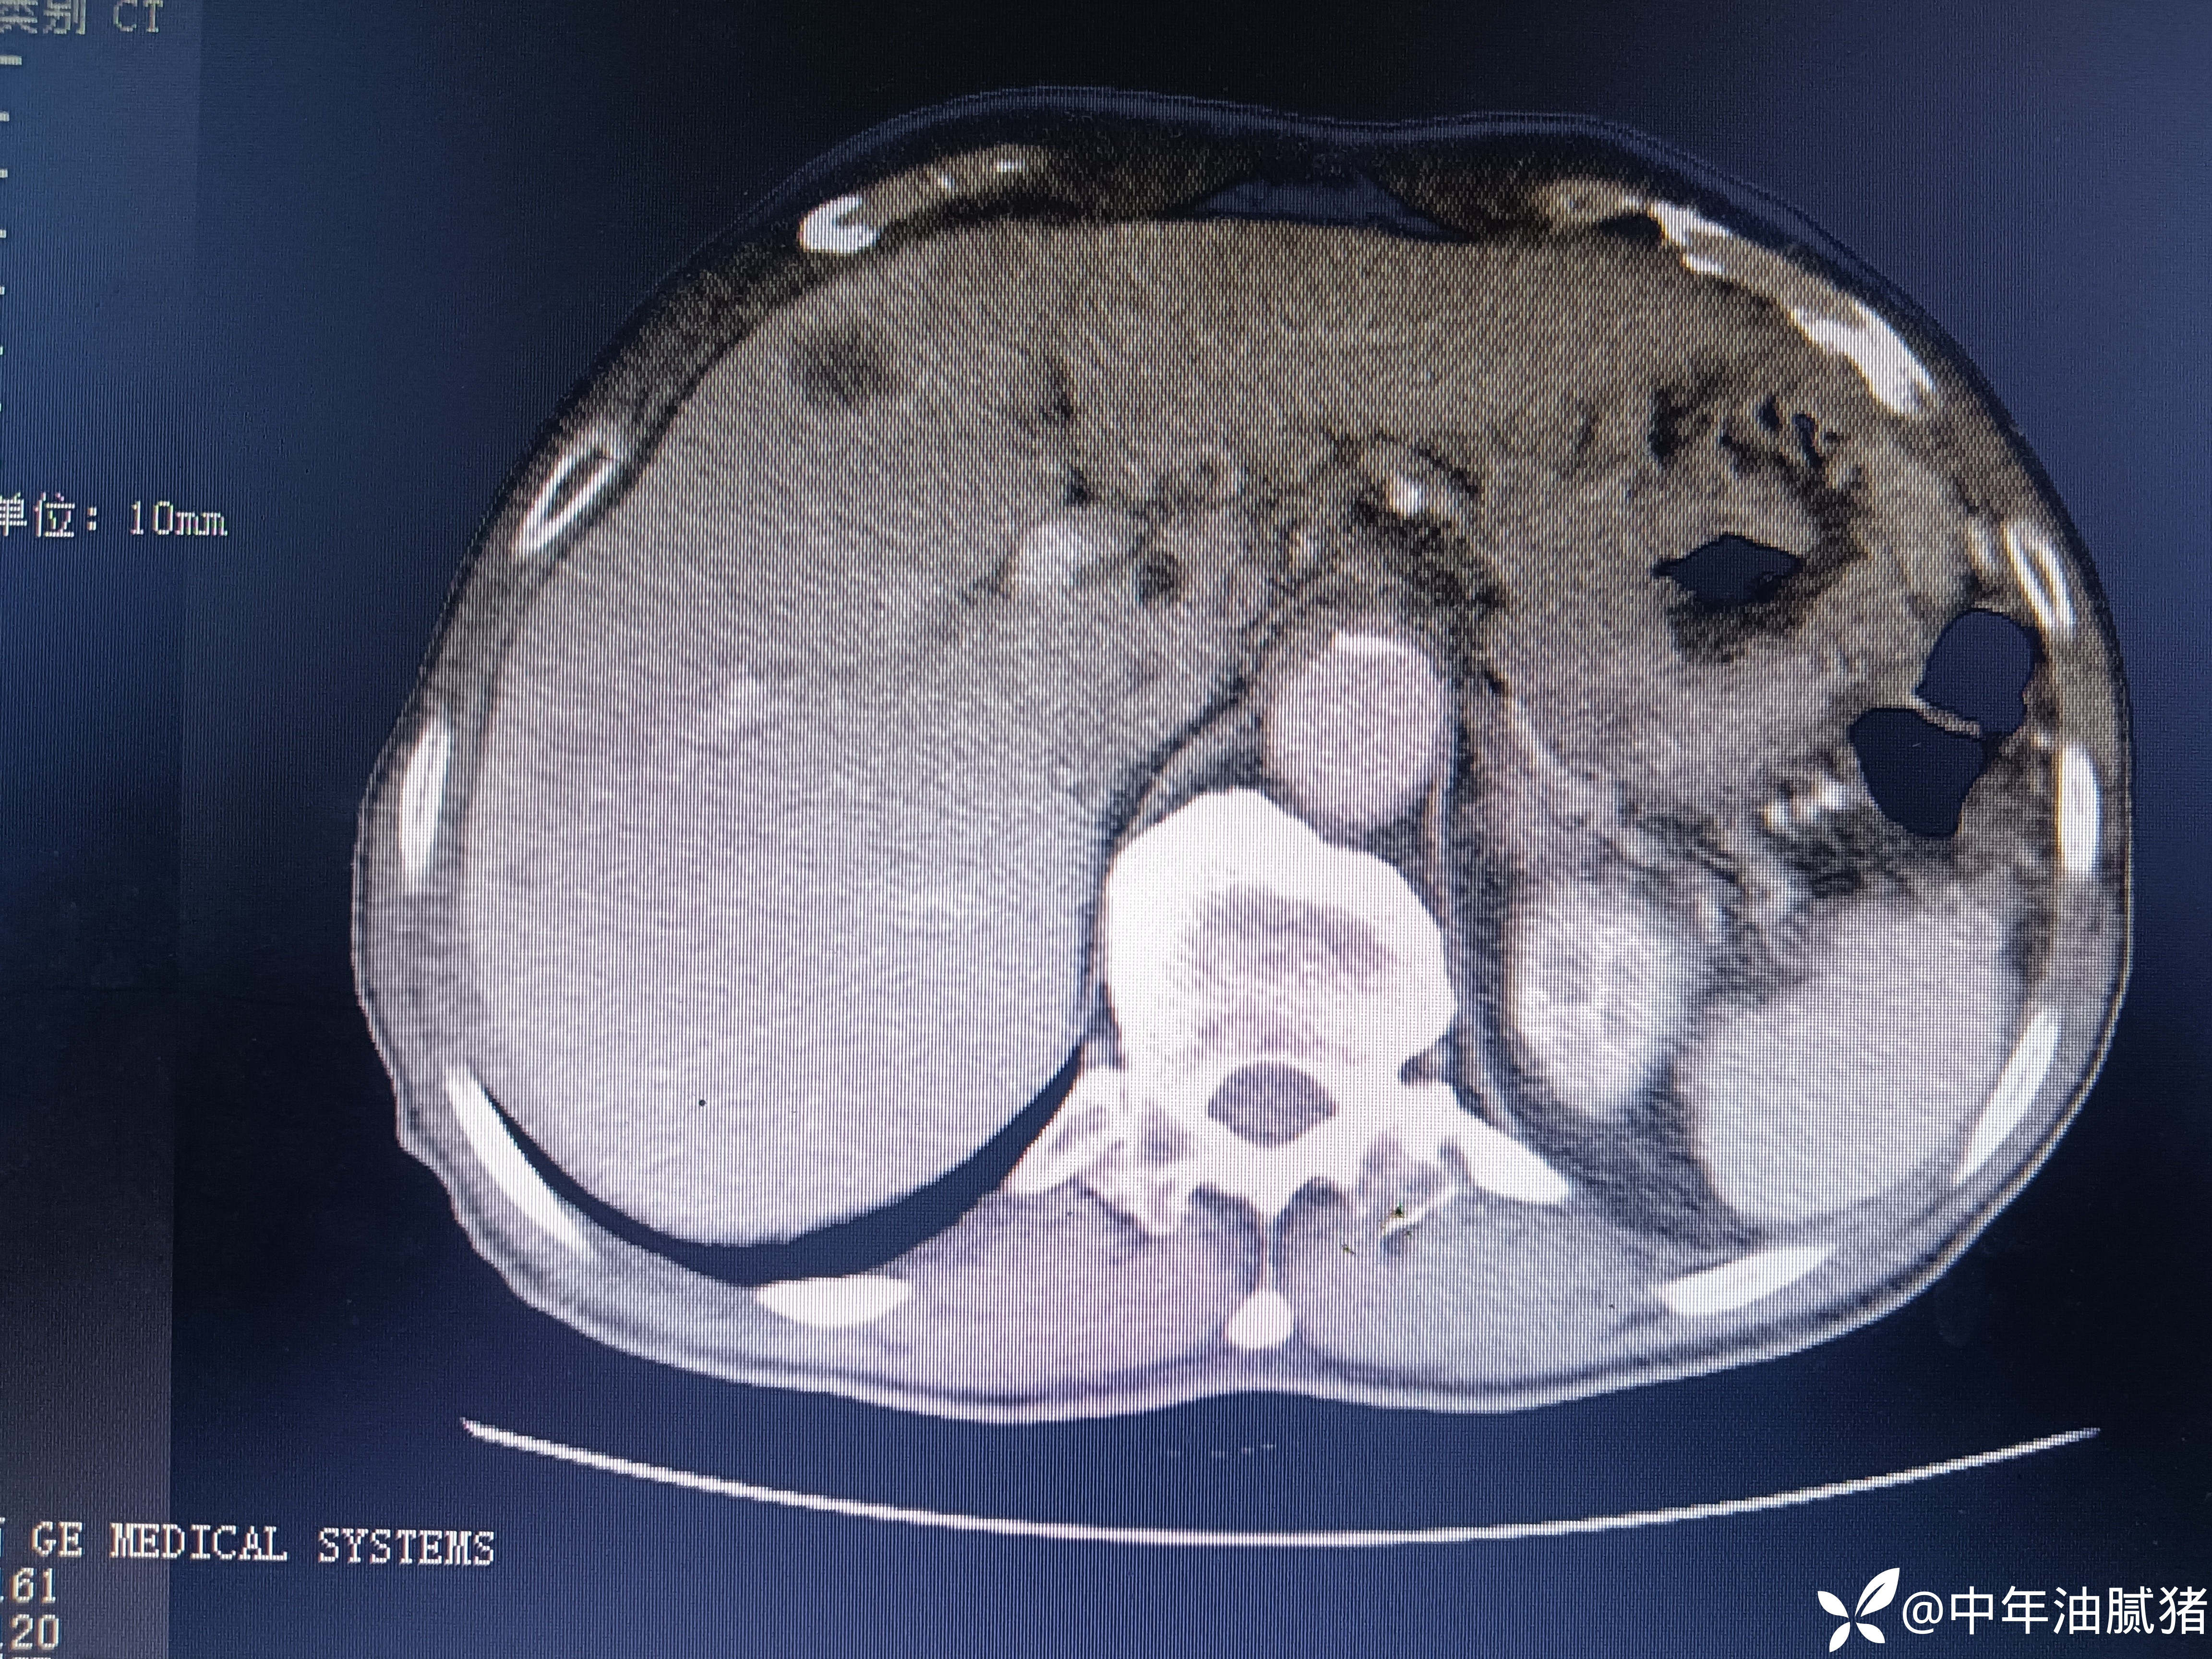

肺ct看到肝内病灶,行增强检查

建议增强ct.报告如下

考虑肝囊肿?让他走?

看后,我隐隐约约觉的不是肝囊肿那么简单?元芳,你怎么看?狄阁老,我也是这么认为!摇人,掏起手机:喂,w主任,请帮我看看这个ct。5分钟后报告修改如下